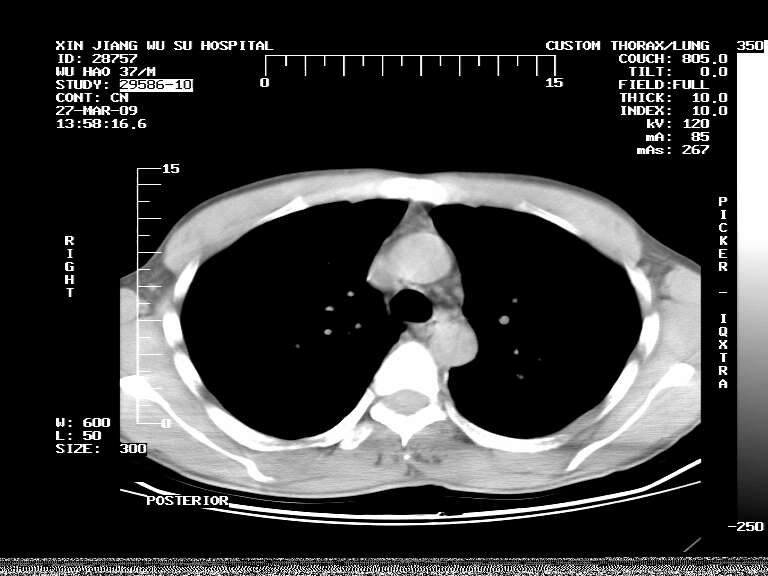

男,37岁,体检胸透发现阴影。

患者体检发现 无症状 左肺下叶占位,边缘模糊,可见血管聚束、分叶、胸膜牵拉,增强呈不均匀性强化。 首先考虑左肺下叶周围型肺癌,建议穿刺活检。

患者体检发现 无症状 左肺下叶占位,边缘模糊,可见血管聚束、分叶、胸膜牵拉,增强呈不均匀性强化。 首先考虑左肺下叶周围型肺癌,建议穿刺活检。支持!

左肺下叶见一结节病变,边缘欠清不光滑,与胸膜粘连且胸膜局限性增厚,注药后呈环形强化,动脉期壁呈明显点环状强化,静脉期壁强化减低,中心密度低无强化,灶周无明显的卫星灶和水肿区(晕征)---考虑周围性肺癌,不除外感染性病变,建议穿刺活检。

周围有卫星灶,胸膜反应不明显,病灶中心有坏死。建议先抗结核治疗后,短期复查